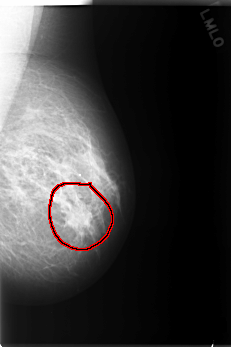

C_0116_1.LEFT_MLO

LEFT_MLO LINES 5896 PIXELS_PER_LINE 3920 BITS_PER_PIXEL 12 RESOLUTION 50 OVERLAY

FILE: C_0116_1.LEFT_MLO.OVERLAY

TOTAL_ABNORMALITIES 1

ABNORMALITY 1

LESION_TYPE MASS SHAPE IRREGULAR MARGINS SPICULATED

ASSESSMENT 5

SUBTLETY 5

PATHOLOGY MALIGNANT

TOTAL_OUTLINES 1

BOUNDARY